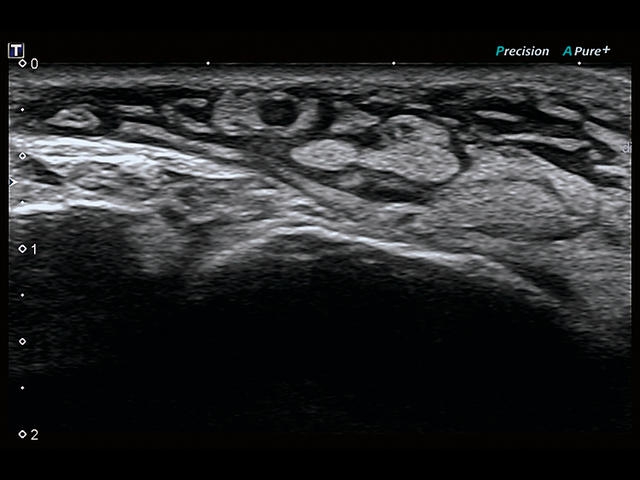

Обновленная версия легендарного УЗ-сканера. Стационарный аппарат экспертного класса Aplio 500 Toshiba NEW, визуализирует анатомические структуры в высоком разрешении. Модель позволяет выявить микрокальцификаты, новообразования, нарушения в работе сердца, сосудов и мышц. Присутствует функция виртуальной эндоскопии, 4D-сканирования, эластометрии тканей, УЗИ с контрастированием. За повышение качества изображения отвечают технологии ApliPure и Superb Microvascular Imaging. Первая задействует возможности пространственного и частотного кодирования, формирует цельный визуальный ряд с сохранением клинических маркеров. Вторая улучшает отображение микрососудистого русла, используя доплеровский эффект. Модель оснащена 21-дюймовым монитором, имеет 4 активных порта. Возможно подключение педиатрических, интраоперационных, лапароскопических и чреспищеводных датчиков.

• D-THI.Режим дифференцированной тканевой гармоники, повышающий качество визуализации глубоко расположенных тканей. Получаемое изображение отличается высокой четкостью, не содержит дефектов в виде «заснеженных» и размытых участков.